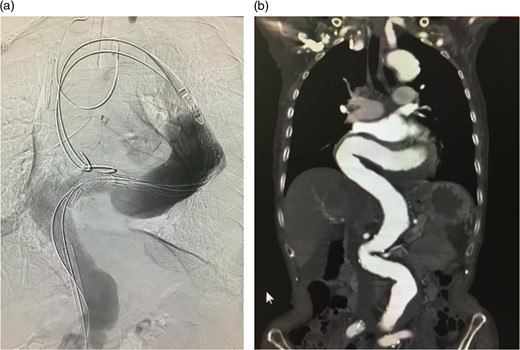

(a) A sheath was introduced and the angulation was slightly reduced. (b) A guide wire was introduced through the sheath. The angulation was further reduced by this procedure. In addition, the angulation of the wire (black arrow), which was used to introduce the stent graft main body, was reduced. Thus, the wire was advanced through the aorta where angulation was small.

The stent graft (Relay Plus® 38 × 34 × 200 mm, Bolton medical, Barcelona) was introduced through the right common femoral artery. When it reached the distal site of the thoracoabdominal aorta where the angulation was the most severe, the outer hard sheath was left there while the inner flexible sheath was advanced. The flexible sheath was successfully introduced to the proximal site of the thoracoabdominal aorta beyond the angulation (Fig. 3). The stent graft was placed and we confirmed that no endoleak existed (Fig. 4).

Intraoperative arteriogram. (a) The hard sheath was left at the distal site of the angulated part and the flexible sheath was advanced. The angulation was sufficiently reduced by additionally introducing delivery devices for the stent graft (sheath and guide wire). Thus, the stent graft was introduced to the proximal side of the angulated part beyond the aneurysm. Compared to the preoperative contrast CT coronal section image (b) a reduction in the angulation of the proximal aneurysm was observed.